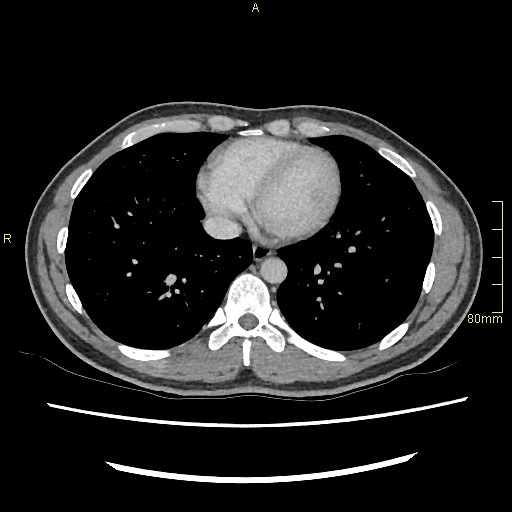

Portal Venous Abdomen (Axial)